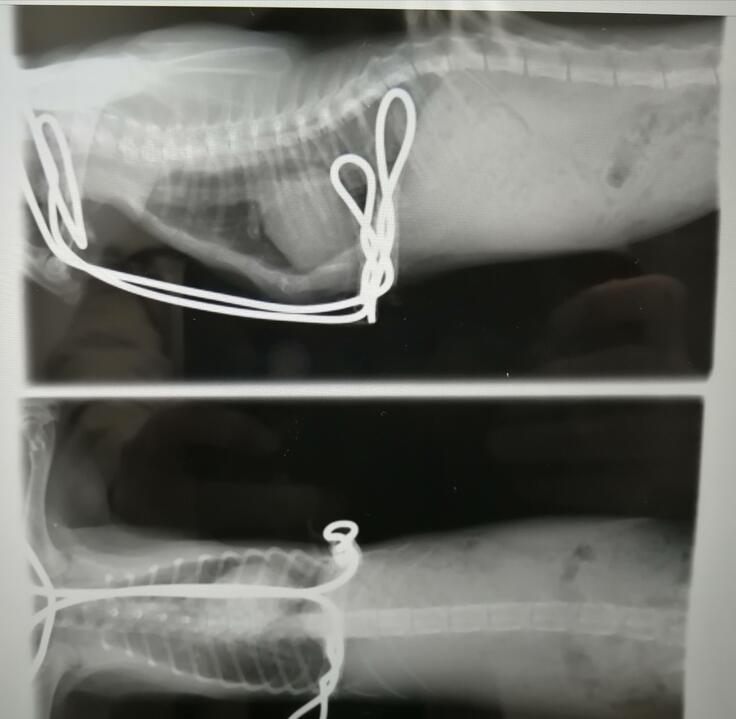

まず、前回掲載できなかった、

二週間前に行ったレントゲンの検査の写真を。

術後4週間で、このように胸骨が変形しました。

手術直後よりも、胸骨が前に飛び出ました。

飛び出ることは問題がないのでよいのですが、

上の画像からは、横隔膜ヘルニアがやはりあること、

下の画像からは、心臓の位置は大きく右にずれたままであることがわかります。(右の肺を大きく圧迫しています。)